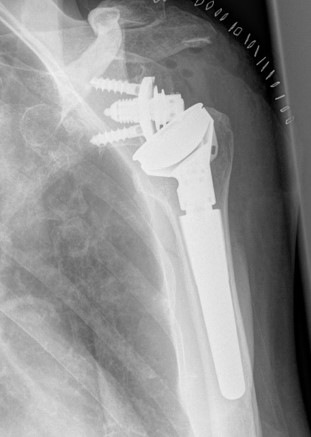

Ist der Verschleiß des Gelenks weit fortgeschritten, ist das Einsetzen eines künstlichen Gelenks, einer sogenannten Endoprothese, erforderlich, um die Beweglichkeit wiederherzustellen und Schmerzen zu lindern. Weitere Gründe für den Einsatz einer Endoprothese sind komplexe Brüche des Oberarmknochens oder der Gelenkpfanne, komplexe Sehnenverletzungen (Rotatorenmanschettenrupturen) sowie unfallbedingte, rheumatisch und tumorbedingte Gelenkschäden. Je nach individuellem Krankheitsbild werden verschiedene Prothesenarten verwendet. Diese sind aus besonders gut verträglichen Materialien wie zum Beispiel Titan gefertigt und zeichnen sich durch eine lange Haltbarkeit aus. Patienten profitieren außerdem von einem verkürzten Genesungsprozess, da Kunstgelenke im Cellitinnen-Krankenhaus Maria-Hilf besonders schonend eingesetzt werden. Hierfür werden minimal-invasive Operationsverfahren genutzt, bei denen Muskeln und Sehnen nicht durchtrennt, sondern lediglich beiseitegeschoben werden. Folgende Arten des Schultergelenkersatzes bietet die Orthopädie des MHK so an:

Eine inverse Schulterendoprothese kommt zum Einsatz, wenn neben der Arthrose auch komplexe Weichteilschäden, wie etwa ein Riss der Rotatorenmanschette, vorliegen. Dabei wird die biomechanische Funktionsweise des Schultergelenks umgekehrt. Das heißt, dass der Oberarmkopf durch eine flache Gelenkpfanne ersetzt wird und die ursprüngliche Gelenkpfanne durch einen kugelartigen Gelenkkopf.